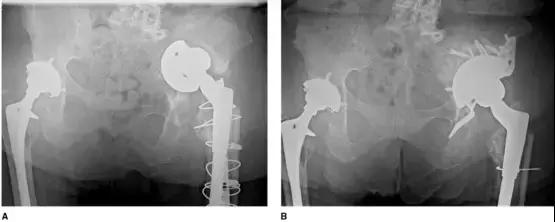

近年来出现了一种新的 cages 与 Jumbo 杯的组合(cup-cage 技术),Jumbo 杯充当垫块的角色,适用于骨盆不连续、骨质量较差的病例,但该技术尚缺乏长期的随访数据(图 6、7)。

图 7 (A)术前骨盆平片显示左髋严重髋臼骨缺损和髋臼假体垂直脱位(B)cup-cage 技术翻修术后骨盆平片